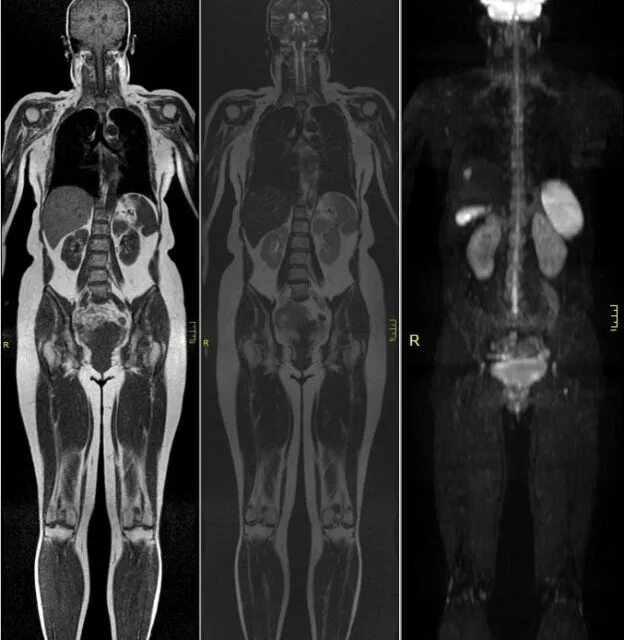

Мрт диффузия всего тела